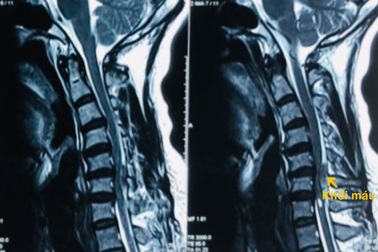

Đột ngột liệt tứ chi vì xuất huyết tủy sống cổNhập viện trong tình trạng đột ngột liệt tứ chi, nam bệnh nhân được bác sĩ xác định bị xuất huyết tủy sống cổ. Đây là bệnh cảnh nguy hiểm, nếu không được phát hiện, can thiệp sớm, nguy cơ tử vong cao.

Thiếu niên 15 tuổi liệt tứ chi sau nhiều giờ dùng điện thoại trong đêmSau nhiều giờ chơi điện thoại trong đêm, thiếu niên 15 tuổi bị đau dữ dội vùng cột sống cổ, liệt tứ chi, phải nhập viện cấp cứu.